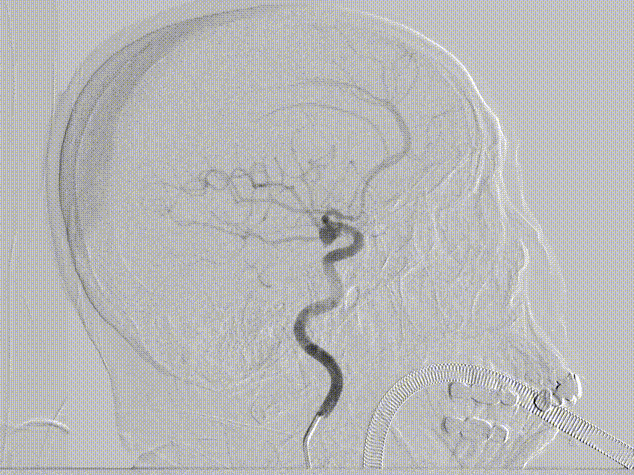

主动脉弓造影:Ⅱ型主动脉弓,双侧椎动脉正侧位造影未见大脑后动脉显影。

右侧颈动脉正侧位造影:可见原始胚胎型大脑后动脉。

左侧颈动脉正侧位造影:左侧颈内动脉后交通段动脉瘤(箭头所示)。